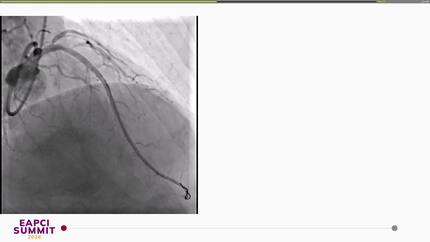

Delayed STEMI-equivalent myocardial infarction due to post-TAVI leaflet obstruction.